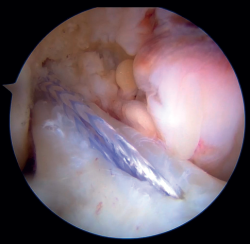

Figura 5. Fijación de suturas en el cóndilo femoral externo mediante implante sin nudos (SwiveLock®, Arthrex). Rodilla izquierda, visión desde el portal anterolateral.

Figura 6. Imagen final de la reparación tras la colocación del InternalBrace® con cinta de alta resistencia. Rodilla izquierda, visión desde el portal anterolateral.